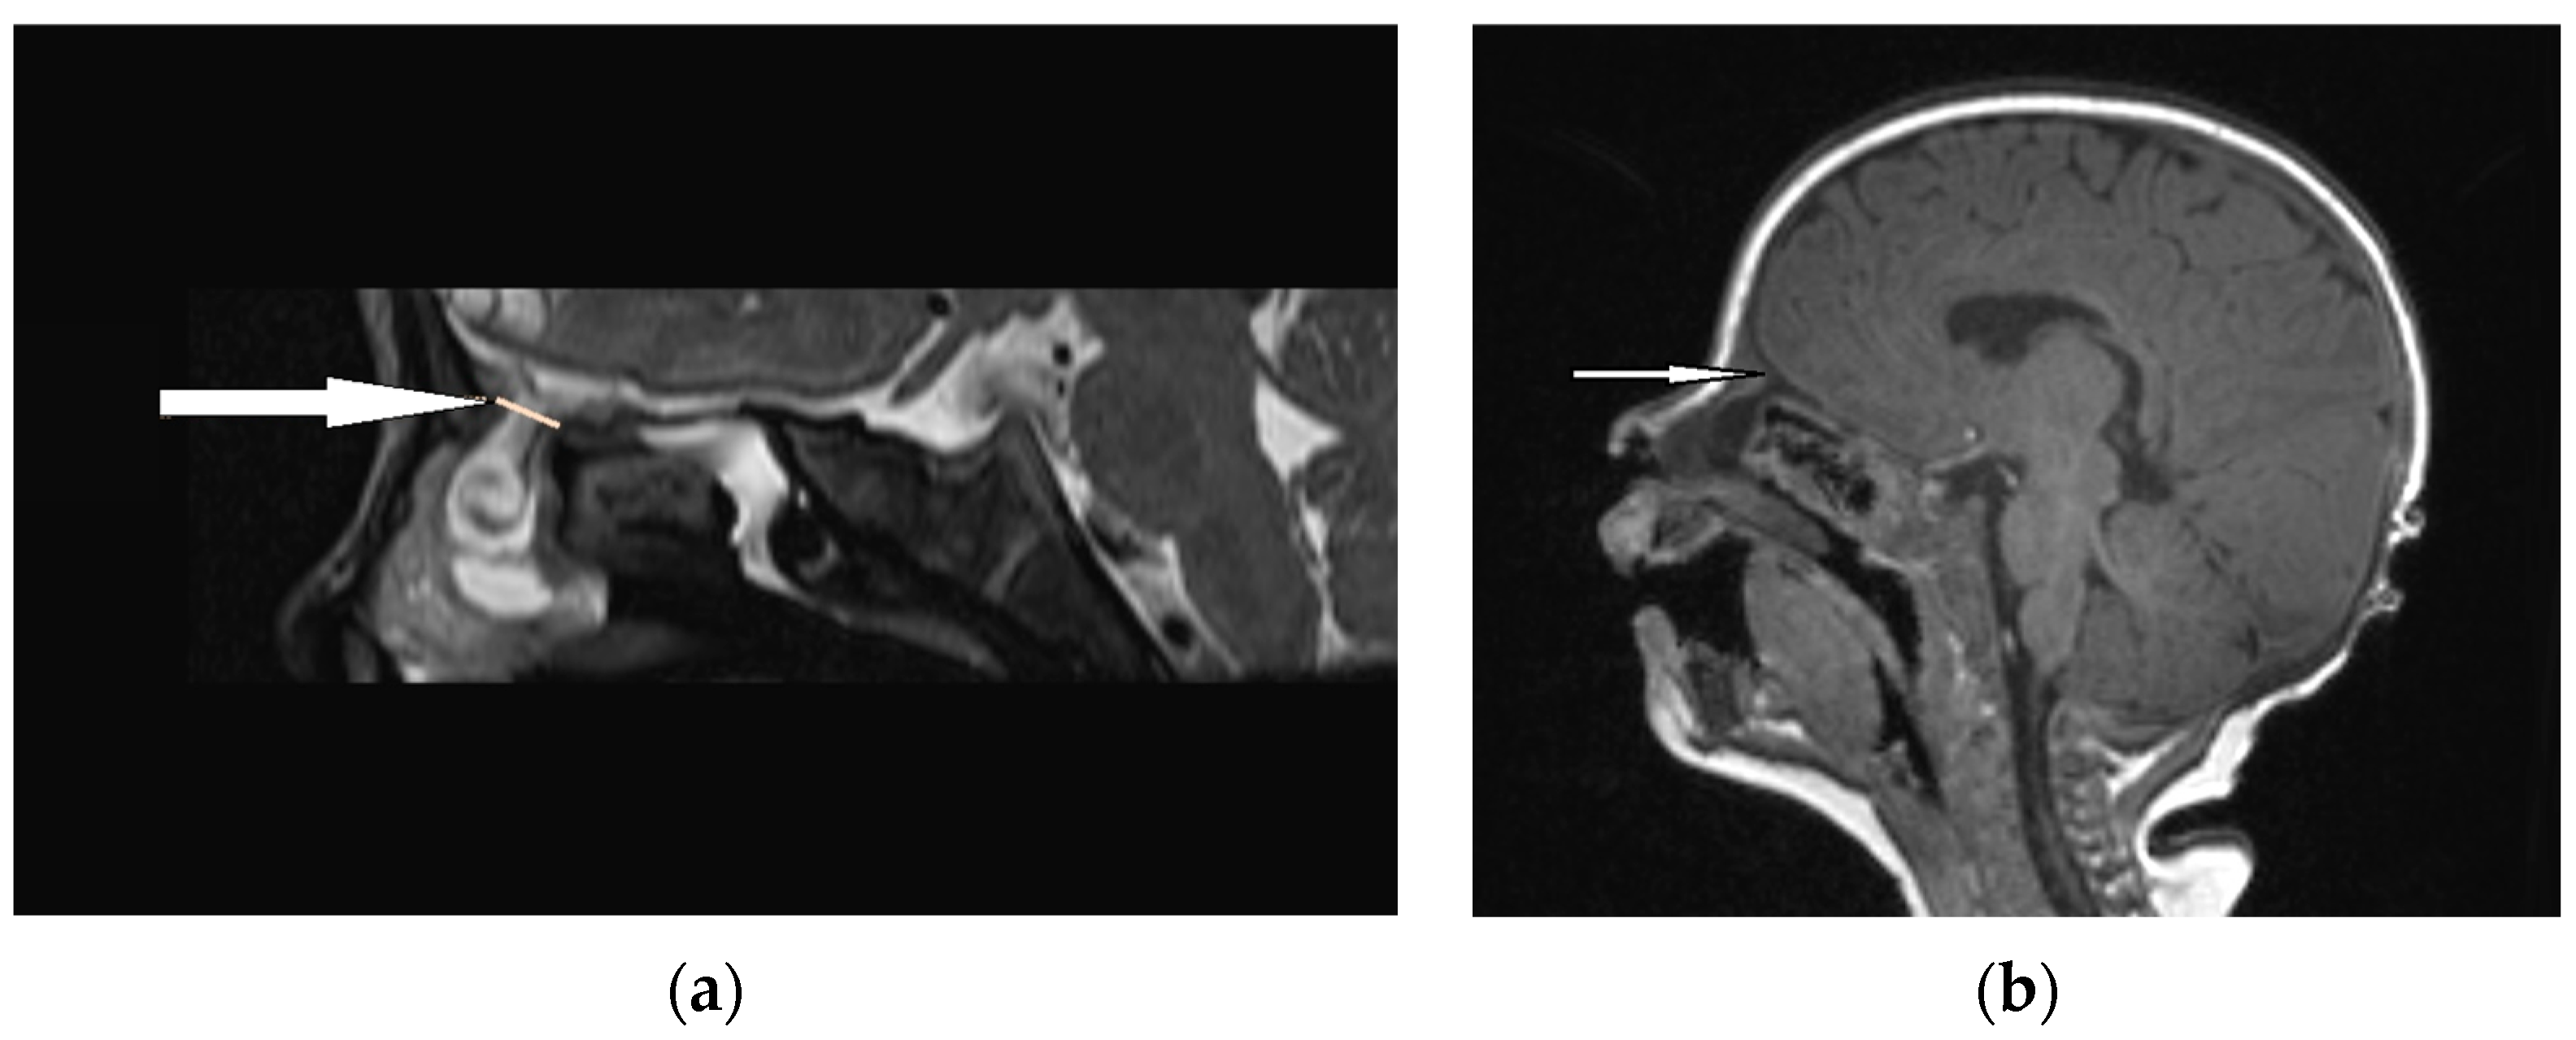

| Radiological characteristics | CT | No correlation between the particular location of the sinus ostium or cyst and the presence of intracranial extension; bifid crista galli and widening of foramen caecum (suggestive of intracranial extension); dermoid cyst—density of fat; epidermoid cyst—density of water | Bony defect may be revelaed | Developmental bony defect of the skull base |

| MRI | Variable signal intensity depending on the protein content; fat-suppressed T1-weighted images—differentiation between skull base defects and enhancing non-ossified cartilage of anterior cranial fossa; DWI—typically high-signal-intensity lesion with corresponding low signal intensity on ADC maps | Discontinuity with the brain parenchyma; variable visualization of a fibrous stalk connection to CNS; well-circumscribed, rounded, or polypoid mass—isointense or rarely hypointense to gray matter on T1-weighted imaging; neural tissue—more hyperintense on T2-weighted images to normal brain parenchyma in most cases; dysplastic tissue usually corresponds with no enhancement or moderate enhancement; noticeable enhancement at the lesion periphery | Herniation of intracranial tissue and its continuity with the brain | |